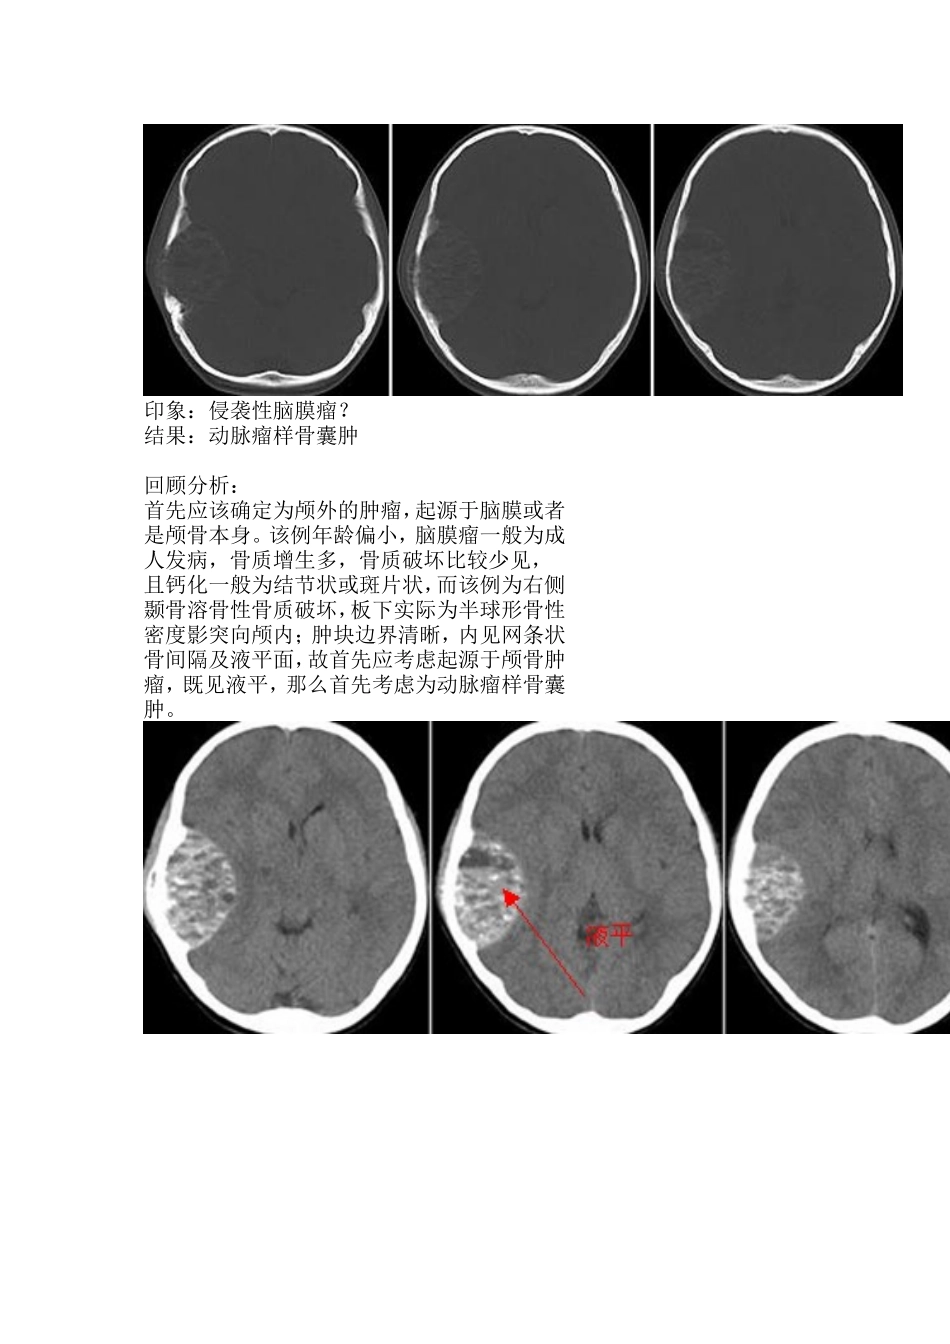

患者女,11岁,3月前无意发现右颞部一蛋黄样大小肿物,伴阵发性头痛,多在活动时出现,偶有头晕,不伴发热、恶心、呕吐,未作治疗,肿物渐增大,头痛、头晕加重印象:侵袭性脑膜瘤?结果:动脉瘤样骨囊肿回顾分析:首先应该确定为颅外的肿瘤,起源于脑膜或者是颅骨本身。该例年龄偏小,脑膜瘤一般为成人发病,骨质增生多,骨质破坏比较少见,且钙化一般为结节状或斑片状,而该例为右侧颞骨溶骨性骨质破坏,板下实际为半球形骨性密度影突向颅内;肿块边界清晰,内见网条状骨间隔及液平面,故首先应考虑起源于颅骨肿瘤,既见液平,那么首先考虑为动脉瘤样骨囊肿。